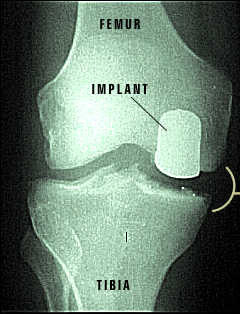

X-ray of Repaired Knee Joint

The partial knee implants have returned this knee joint to its normal functioning. You can see the difference made by the implants when compared to the damaged knee before surgery.